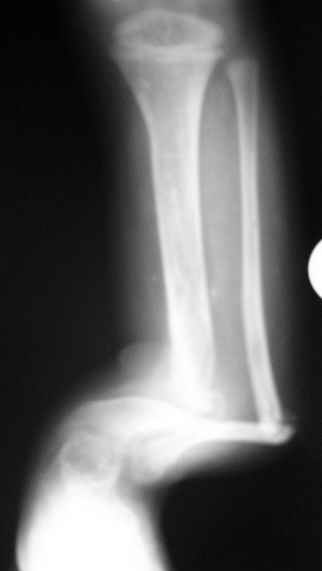

Congenital tibial pseudoarthrosis |

Госпитализировали ребенка 4 лет с врожденной деформацией голени.

Нога опороспособна, безболезненна, выраженная хромота за счет укорочения.